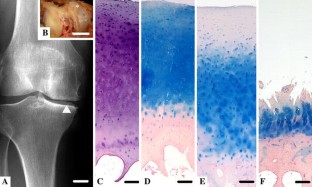

Fig. 1